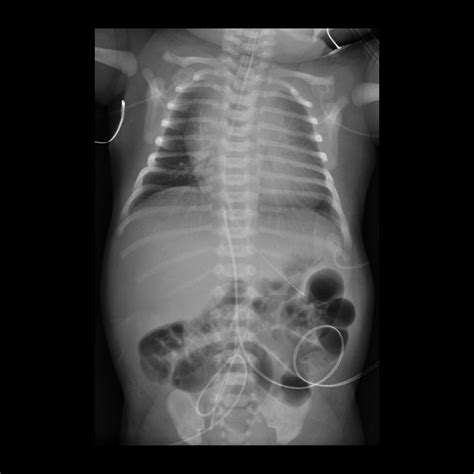

3. Insertion: The catheter is gently inserted into the umbilical vein, which is identified by its larger size and bluish color compared to the arteries. The catheter is advanced until it reaches the desired position, typically confirmed by ultrasound or X-ray.

5. Verification: The position of the catheter is verified using imaging techniques to ensure it is correctly placed in the inferior vena cava.

• Thrombosis: Blood clots can form around the catheter, leading to vascular occlusion or embolism.

• Malposition: Incorrect placement of the catheter can lead to ineffective therapy or complications such as arrhythmias.